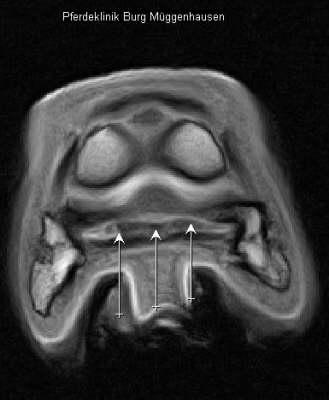

Querschnitt durch den Huf auf Höhe des unteren Strahlbeinbandes. Die drei Pfeile markieren das untere Strahlbeinband, der linke Pfeil deutet auf einen Schaden im Band (helle Zone).